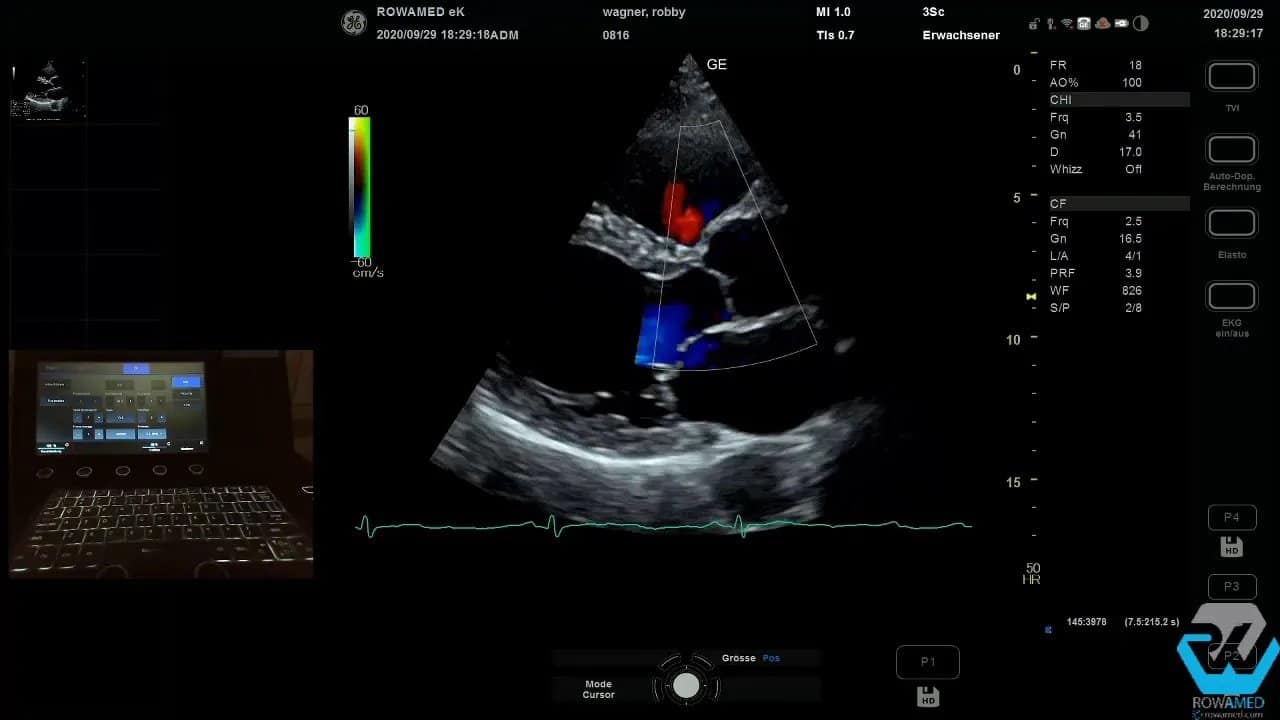

Step 3: Die linke Ventrikelfunktion und erste Klappenbefunde beurteilen

Noch in der parasternal langen Achse können Sie die globale Kinetik des linken Ventrikels sehr gut einschätzen. Schon ohne aufwendige Nachbearbeitung fällt oft auf, ob der Ventrikel homogen kontrahiert oder regionale Wandbewegungsstörungen vorliegen.

Wenn bereits eine bekannte Klappeninsuffizienz im Raum steht, schalten Sie jetzt den Farbdoppler dazu. Das ist in der Transthorakale Echokardiographie der schnellste Weg, um einen ersten funktionellen Eindruck zu bekommen.

Im Beispiel bestand der Verdacht auf eine Aortenklappeninsuffizienz. Im Farbdoppler zeigte sich jedoch keine relevante Aorteninsuffizienz. Stattdessen fiel eine kleine Mitralinsuffizienz auf. Auch das ist typisch: Der erste Verdacht bestätigt sich nicht immer, und manchmal findet man die eigentliche Auffälligkeit an anderer Stelle.

Wichtig bei der Farbdoppler-Beurteilung:

- Skalierung und Farbbereich passend einstellen

- auf Aliasing und technische Artefakte achten

- nicht nur auf die Jet-Länge schauen

- vor allem die Jet-Breite an der Durchtrittsebene berücksichtigen

Ein langer Jet wirkt schnell eindrucksvoll. Für die Schweregradbeurteilung ist aber entscheidend, wie breit die Regurgitation direkt an der Klappe ansetzt. Ein oben schmaler Jet kann trotz größerer Ausdehnung im Vorhof nur geringgradig sein.

Step 11: Klappeninsuffizienzen richtig einordnen

Bei der Mitralklappe zeigte sich ein relativ kräftig wirkender Jet, der an der Durchtrittsebene jedoch sehr schmal war. Das spricht für eine geringe bis allenfalls mittelgradige Mitralinsuffizienz. Genau an dieser Stelle passieren viele Fehleinschätzungen. Wer nur auf die Länge des Jets blickt, überschätzt leicht den Schweregrad.

Für die Standarduntersuchung reicht häufig die semiquantitative Beurteilung. Eine weitergehende Quantifizierung wäre möglich, würde aber über den Basiskatalog hinausgehen.

Noch wichtiger ist ein methodischer Grundsatz: Regurgitationen immer in mehreren Ebenen beurteilen. In nur einer Projektion können Sie Klappeninsuffizienzen deutlich unter- oder überschätzen. Deshalb wurde die Mitralinsuffizienz zusätzlich in einer zweiten und dritten Ebene kontrolliert. Überall zeigte sich derselbe Eindruck: ein schmaler Jet, nicht problematisch, vereinbar mit einer geringgradigen Insuffizienz.